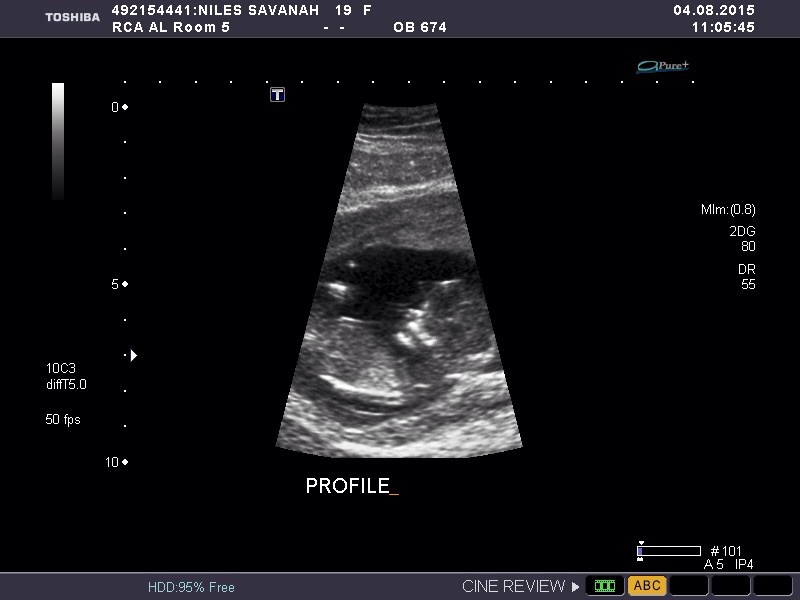

12 week scan. EDD is 2/20 so I'm measuring a little further along at 12wk 5d. HR was 177 and baby was moving and dancing around in there like crazy! So neat to see.